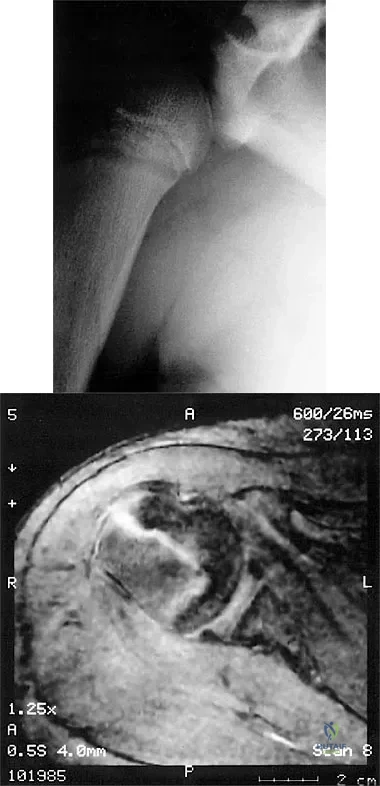

Question 48

A 14-year-old boy sustains a twisting injury to his right shoulder and recalls feeling a snap during a wrestling match. Examination shows hesitancy to raise the arm away from the side, diffuse tenderness and swelling of the upper arm, and no evidence of neurovascular compromise. Figures 6a and 6b show an AP radiograph and MRI scan. What is the most likely diagnosis?

Explanation